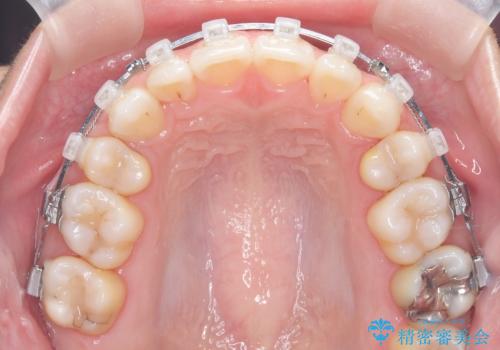

- 治療計画

上下左右の第一小臼歯を抜歯し、クリアブラケット(白い装置)とメタルワイヤーを使用して矯正を開始。初期には犬歯のアーチ内への整列を優先し、中盤からは前歯と奥歯の咬合関係の調整を進めました。審美性に優れた装置を使用したことで、治療中も目立ちにくく、見た目へのストレスが少ない点も評価されています。全体の治療は1年半で完了し、見た目・噛み合わせともに大きく改善。患者本人も「短期間でここまで変わるとは思わなかった」と満足されていました。